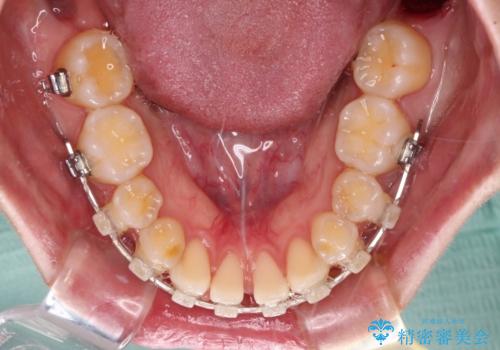

下顎前歯の欠損歯列 ワイヤー装置での矯正治療

下顎前歯が2歯欠損しており、スペースになっており、上顎は叢生歯列となってしました。

当初は上記計画でしたが、レントゲン撮影よりインプラント埋入は困難と判断され、患者様と相談の上、歯を削ってブリッジとするよりも、奥歯の咬み合わせを多少妥協することとなっても、スペースを閉じて仕上げていくこととしました。